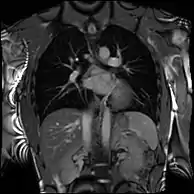

Partial Anomalous Pulmonary Venous Drainage by CMR